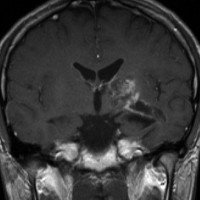

再発ジャーミノーマの画像です。延髄背側の閂 ovexという部位に再発しています。

このパターンはとても多いです。なぜかというと,全脳室照射の時に,第4脳室下端のovexの上衣 ependyum を照射野に入れない放射線治療医の先生がいるからです。放射線科の先生にもちょっとした知識が必要なのです。

これは再治療で腫瘍が消えても不可逆的な重症の延髄障害を残してしまいます。